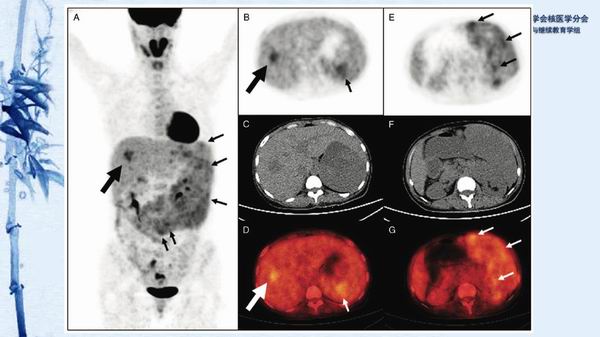

病例81:原发性脾血管肉瘤伴肝血管瘤一例-【CSNM继教学组】郑堃 北京协和医院